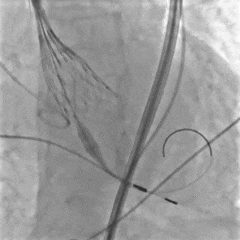

右侧入路造影

6mm外周球囊扩张狭窄处

造影定位球囊位置

再次扩张狭窄段

扩张后造影

大鞘置入至降主动脉